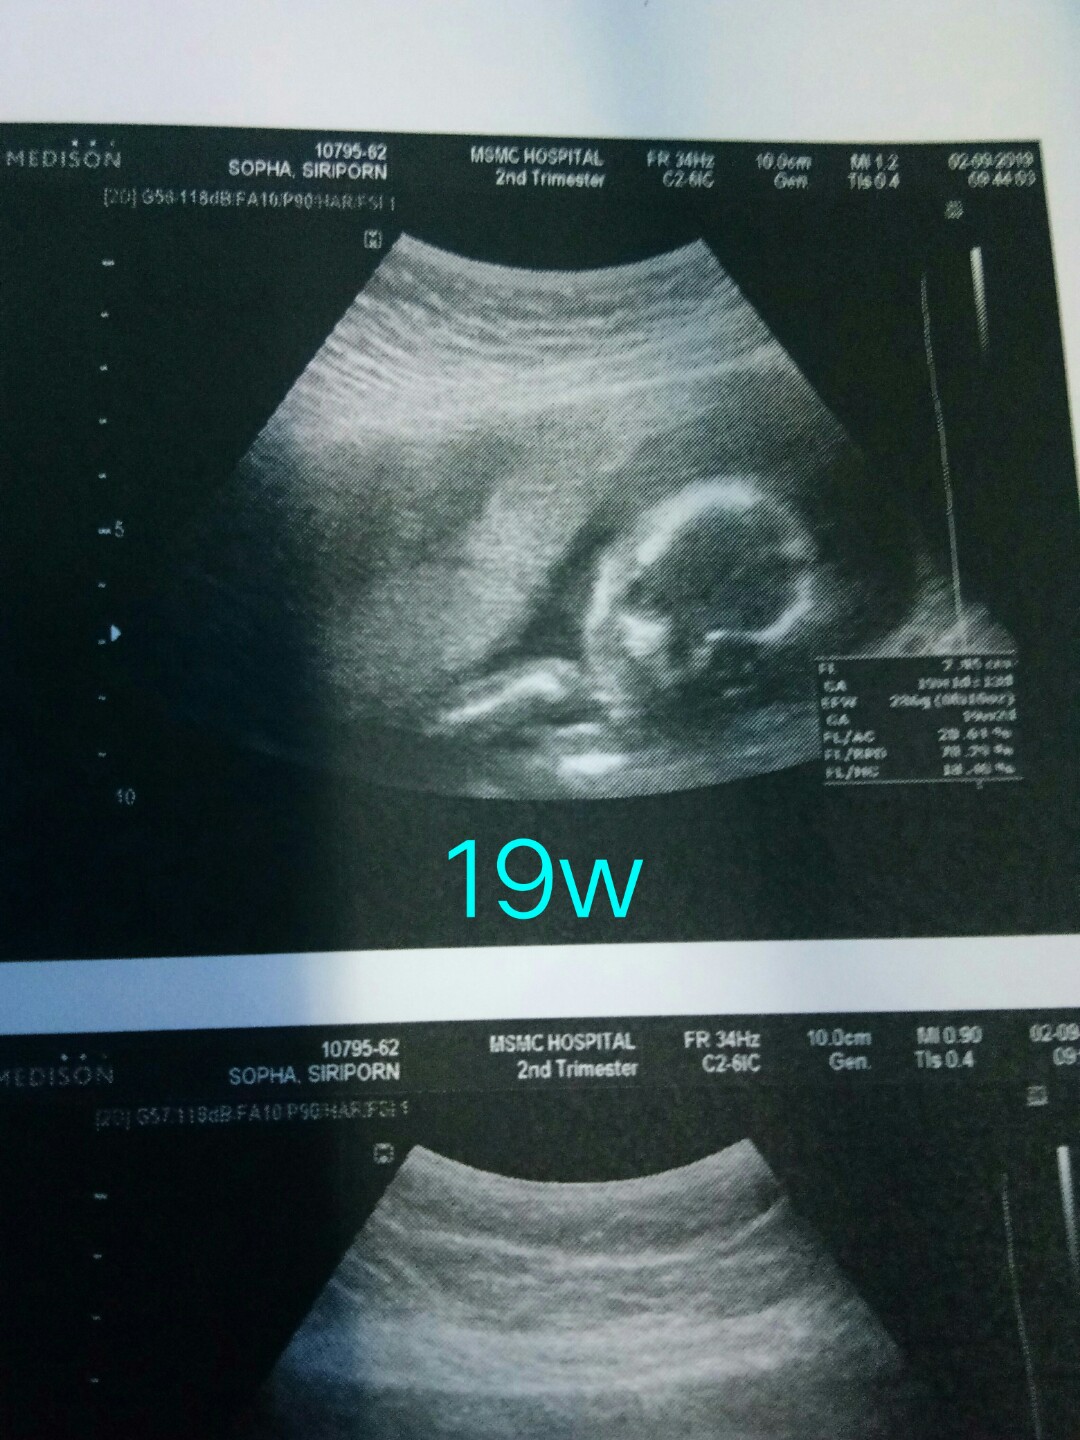

19w

19weekจ้า